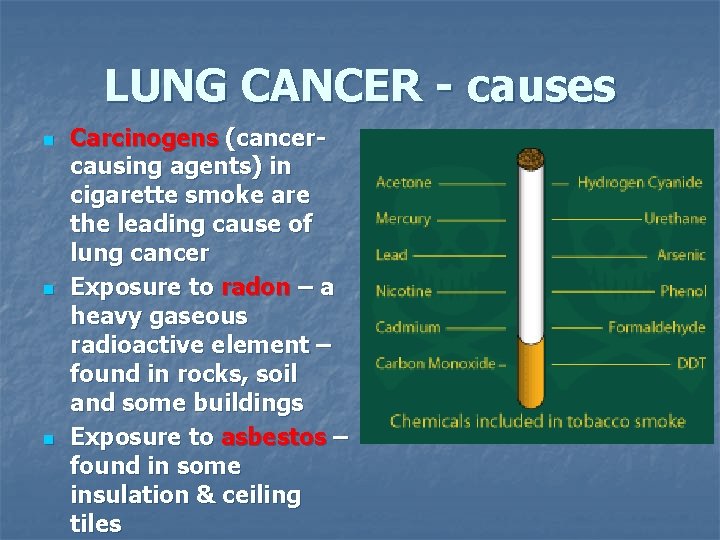

LUNG CANCER - causes n n n Carcinogens (cancercausing agents) in cigarette smoke are the leading cause of lung cancer Exposure to radon – a heavy gaseous radioactive element – found in rocks, soil and some buildings Exposure to asbestos – found in some insulation & ceiling tiles